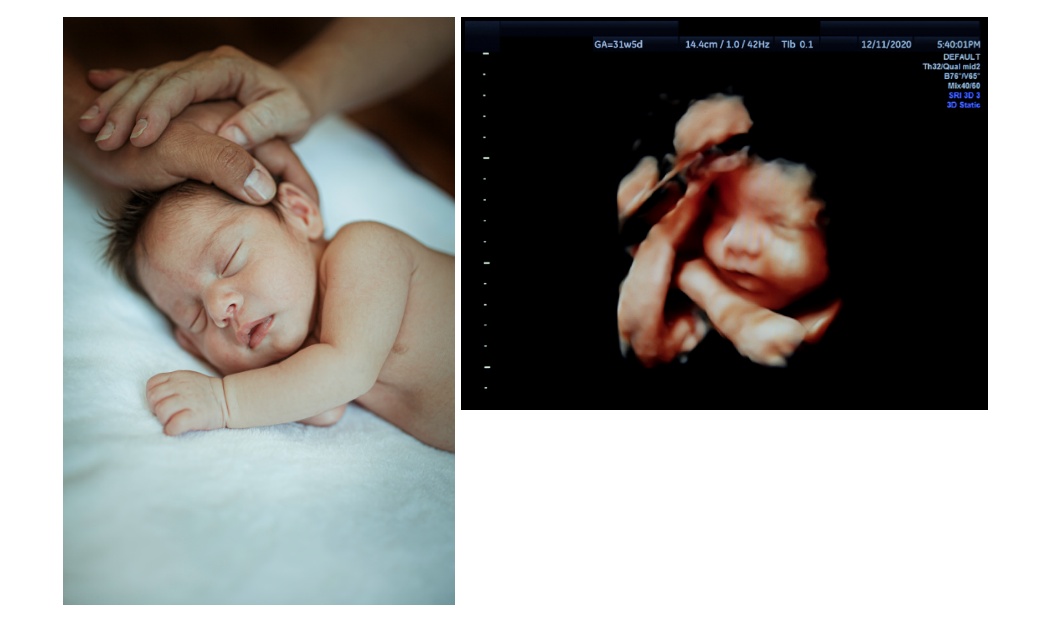

Още 6 момченца се родиха през последните 6 седмици, благодарение на Програмата, инициирана от кмета на София Йорданка Фандъкова и фондация „Майки за донорство“ за подпомагане на двойки с репродуктивни проблеми, нуждаещи се от инвитро процедури с донорски яйцеклетки.

С тях родените бебета станаха 42, от които момчетата са 26, а момиченцата - 16.